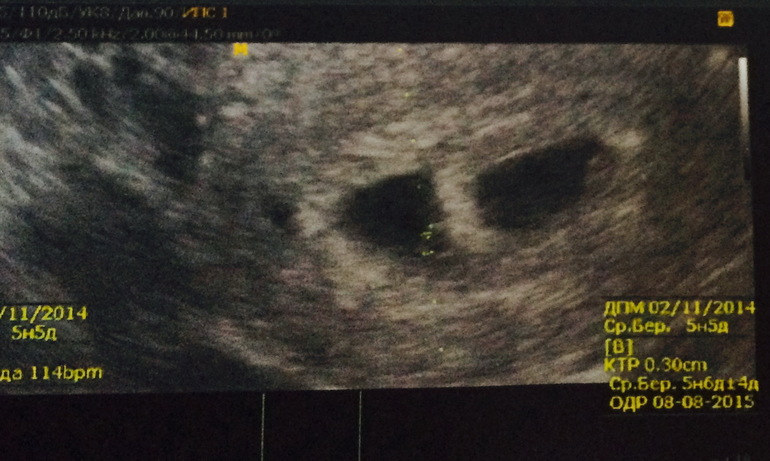

Сдала Хгч еще до первого узи, где то на 10 дпп, сравнила с таблицей ( здесь где-то находила) и заподозрила , что прикрепилось всё - таки два эмбриошки. Птм начались кармические совпадения) то птица в окно два раза ударится, то рыбки у нас дома появились случайным образом в количестве двух штук и прочее. В 6 нед на узи подтвердили 2 плодных яйца